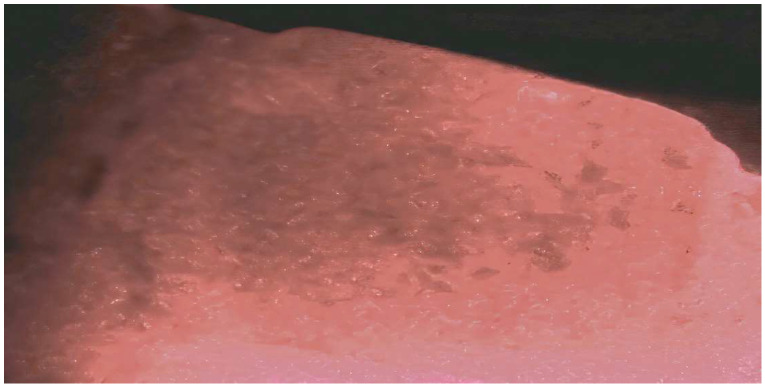

Results: The published literature supports that calculus is a major risk factor for periodontal inflammation. Recent studies indicate that the pathologic risk of calculus goes beyond the retention of biofilm and may represent a different pathophysiologic pathway for periodontal disease separate from the direct action of biofilm. The inadequate removal of calculus is a factor in the failure of periodontal therapy.

Conclusions: The inadequate removal of calculus plays an important role in the frequent failure of non-surgical periodontal therapy to eliminate inflammation.